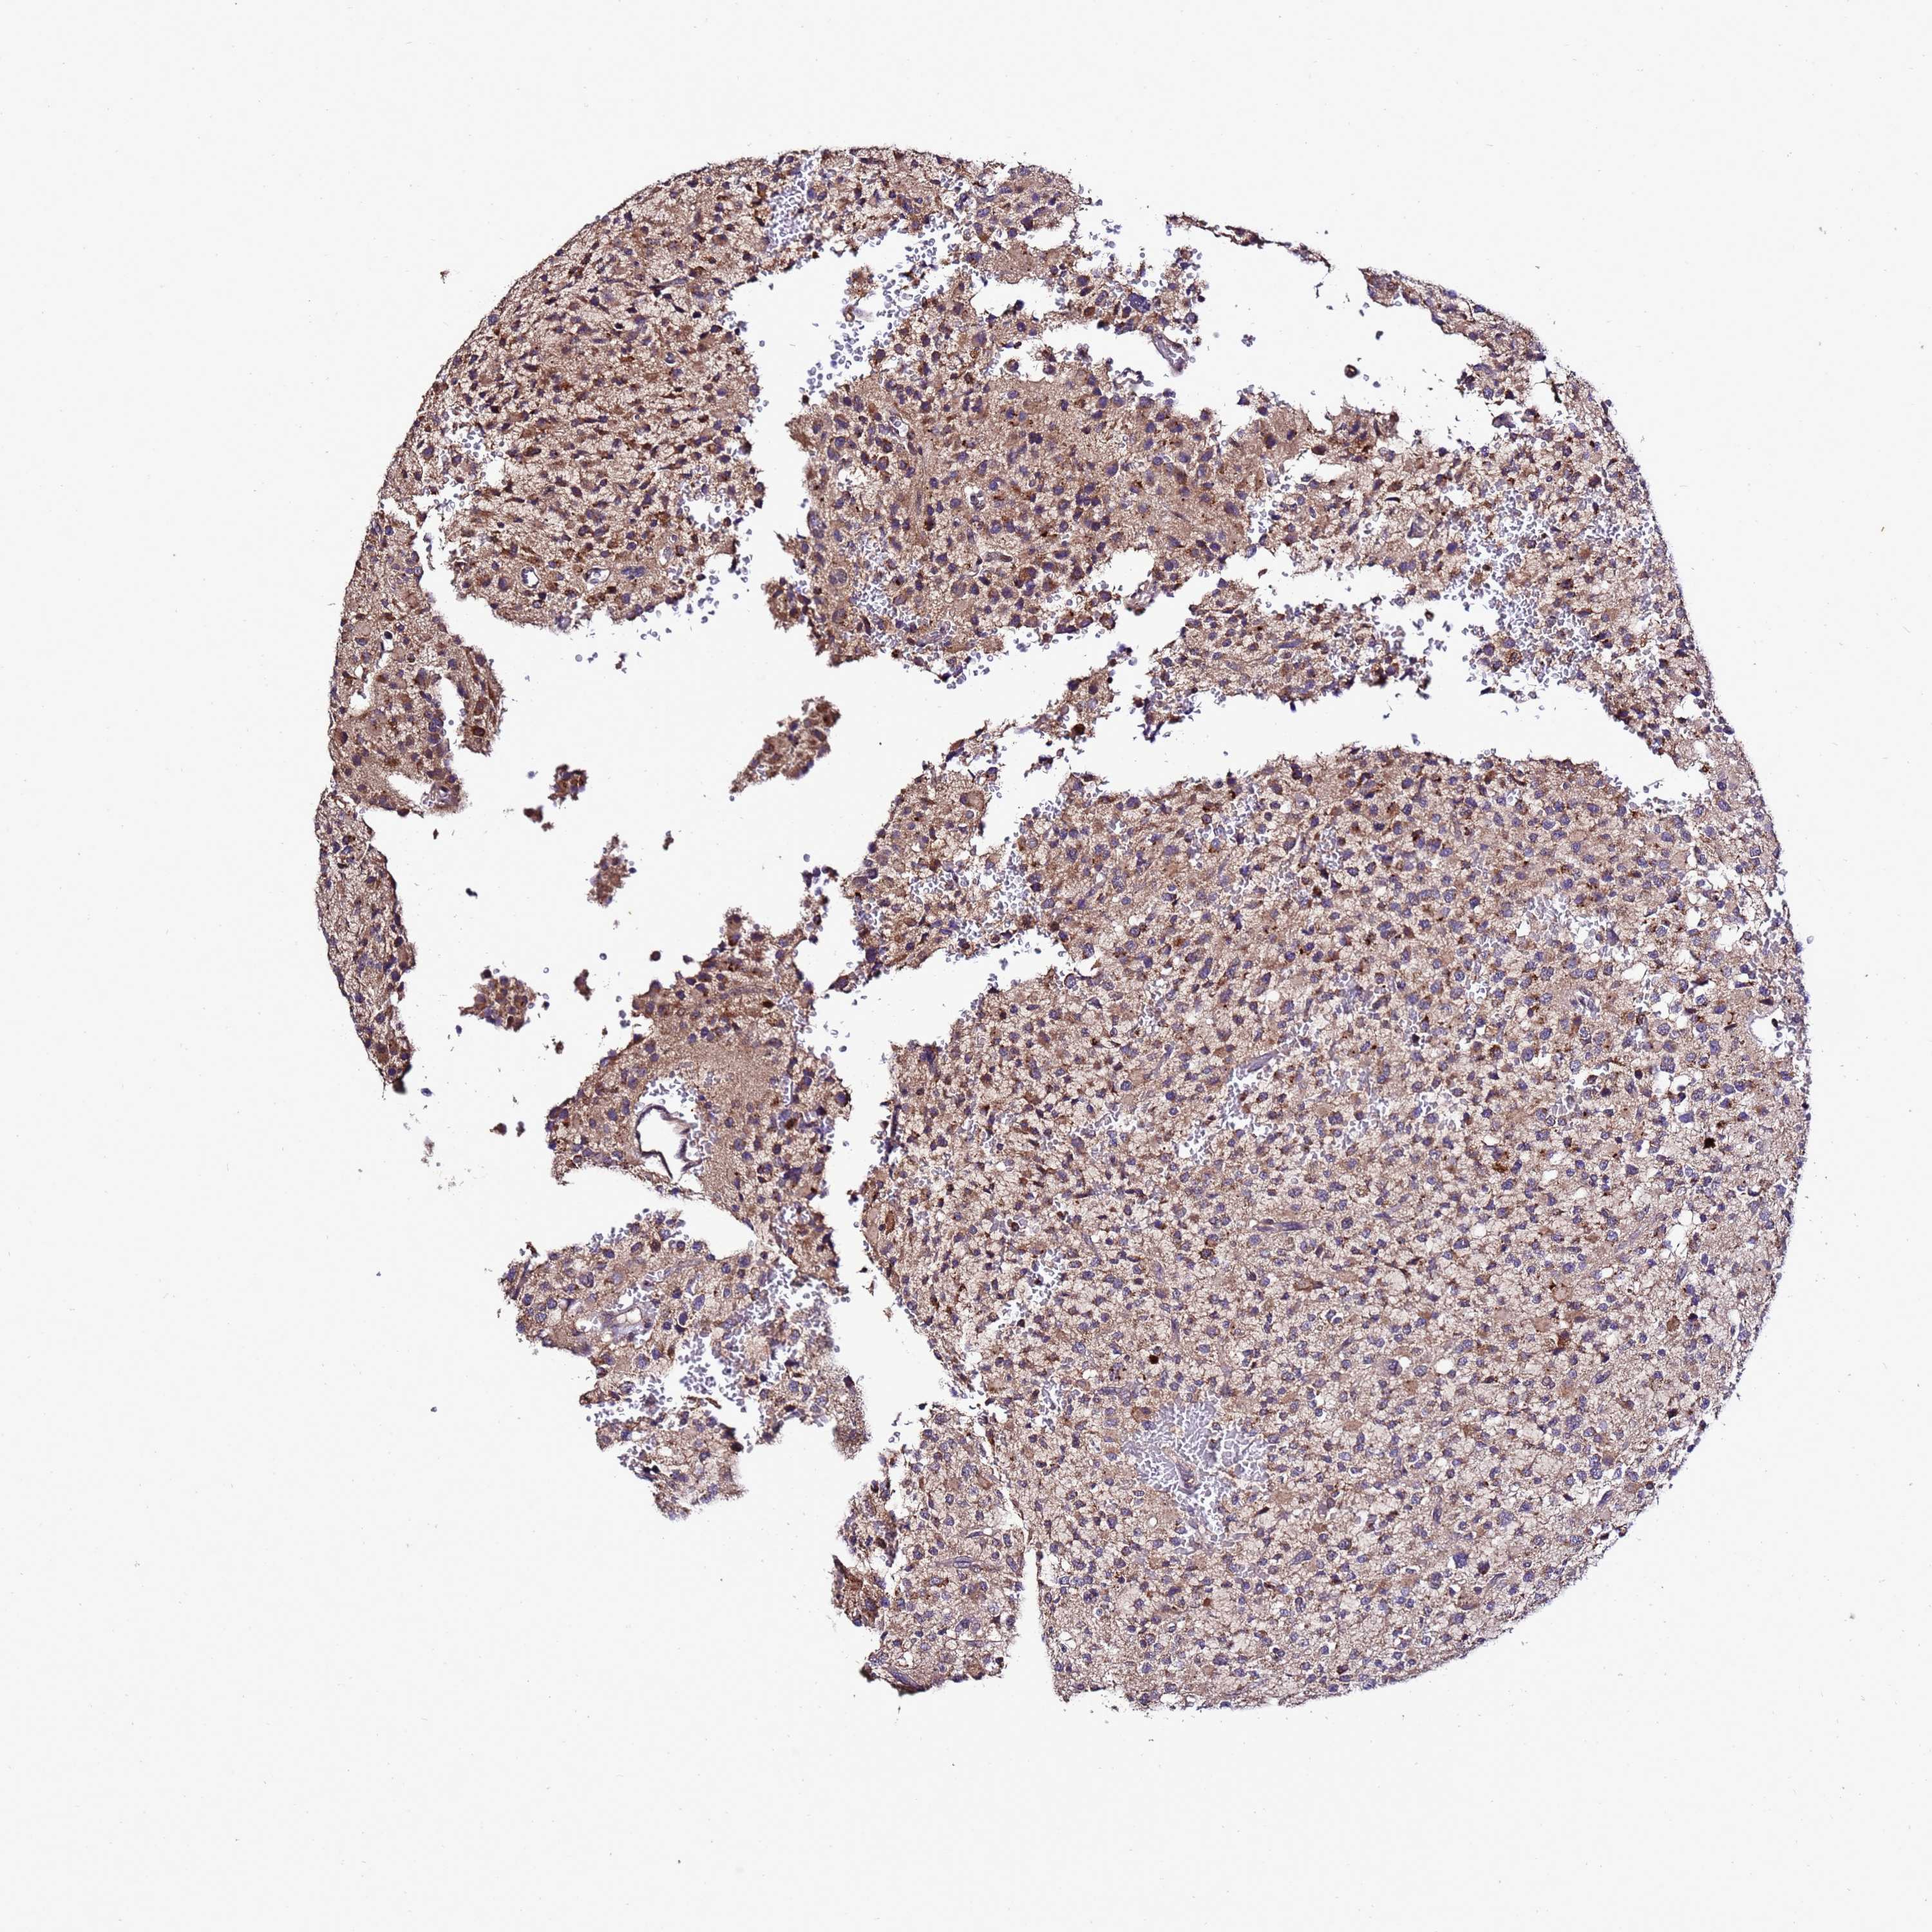

GLIOMA - Protein expressioni

A mouse-over function shows sample information and annotation data. Click on an image to view it in a full screen mode. Samples can be filtered based on level of antibody staining by selecting one or several of the following categories: high, medium, low and not detected. The assay and annotation is described here.

Note that samples used for immunohistochemistry by the Human Protein Atlas do not correspond to samples in the TCGA dataset.

Antibody stainingi

Antibody staining in the annotated cell types in the current human tissue is reported as not detected, low, medium, or high, based on conventional immunohistochemistry profiling in selected tissues. This score is based on the combination of the staining intensity and fraction of stained cells.

Each image is clickable and will lead to virtual microscopy that enables deeper exploration of all samples and also displays staining intensity scores, fraction scores and subcellular localization as well as patient and tissue information for each sample.

Antibody HPA044373

Staining

High

Medium

Low

Not detected

Intensity

Strong

Moderate

Weak

Negative

Quantity

>75%

75%-25%

<25%

None

Location

Nuclear

Cytoplasmic/membranous

Cytoplasmic/membranous,nuclear

Glioma, malignant, High grade

Glioma, malignant, Low grade

Glioblastoma, NOS